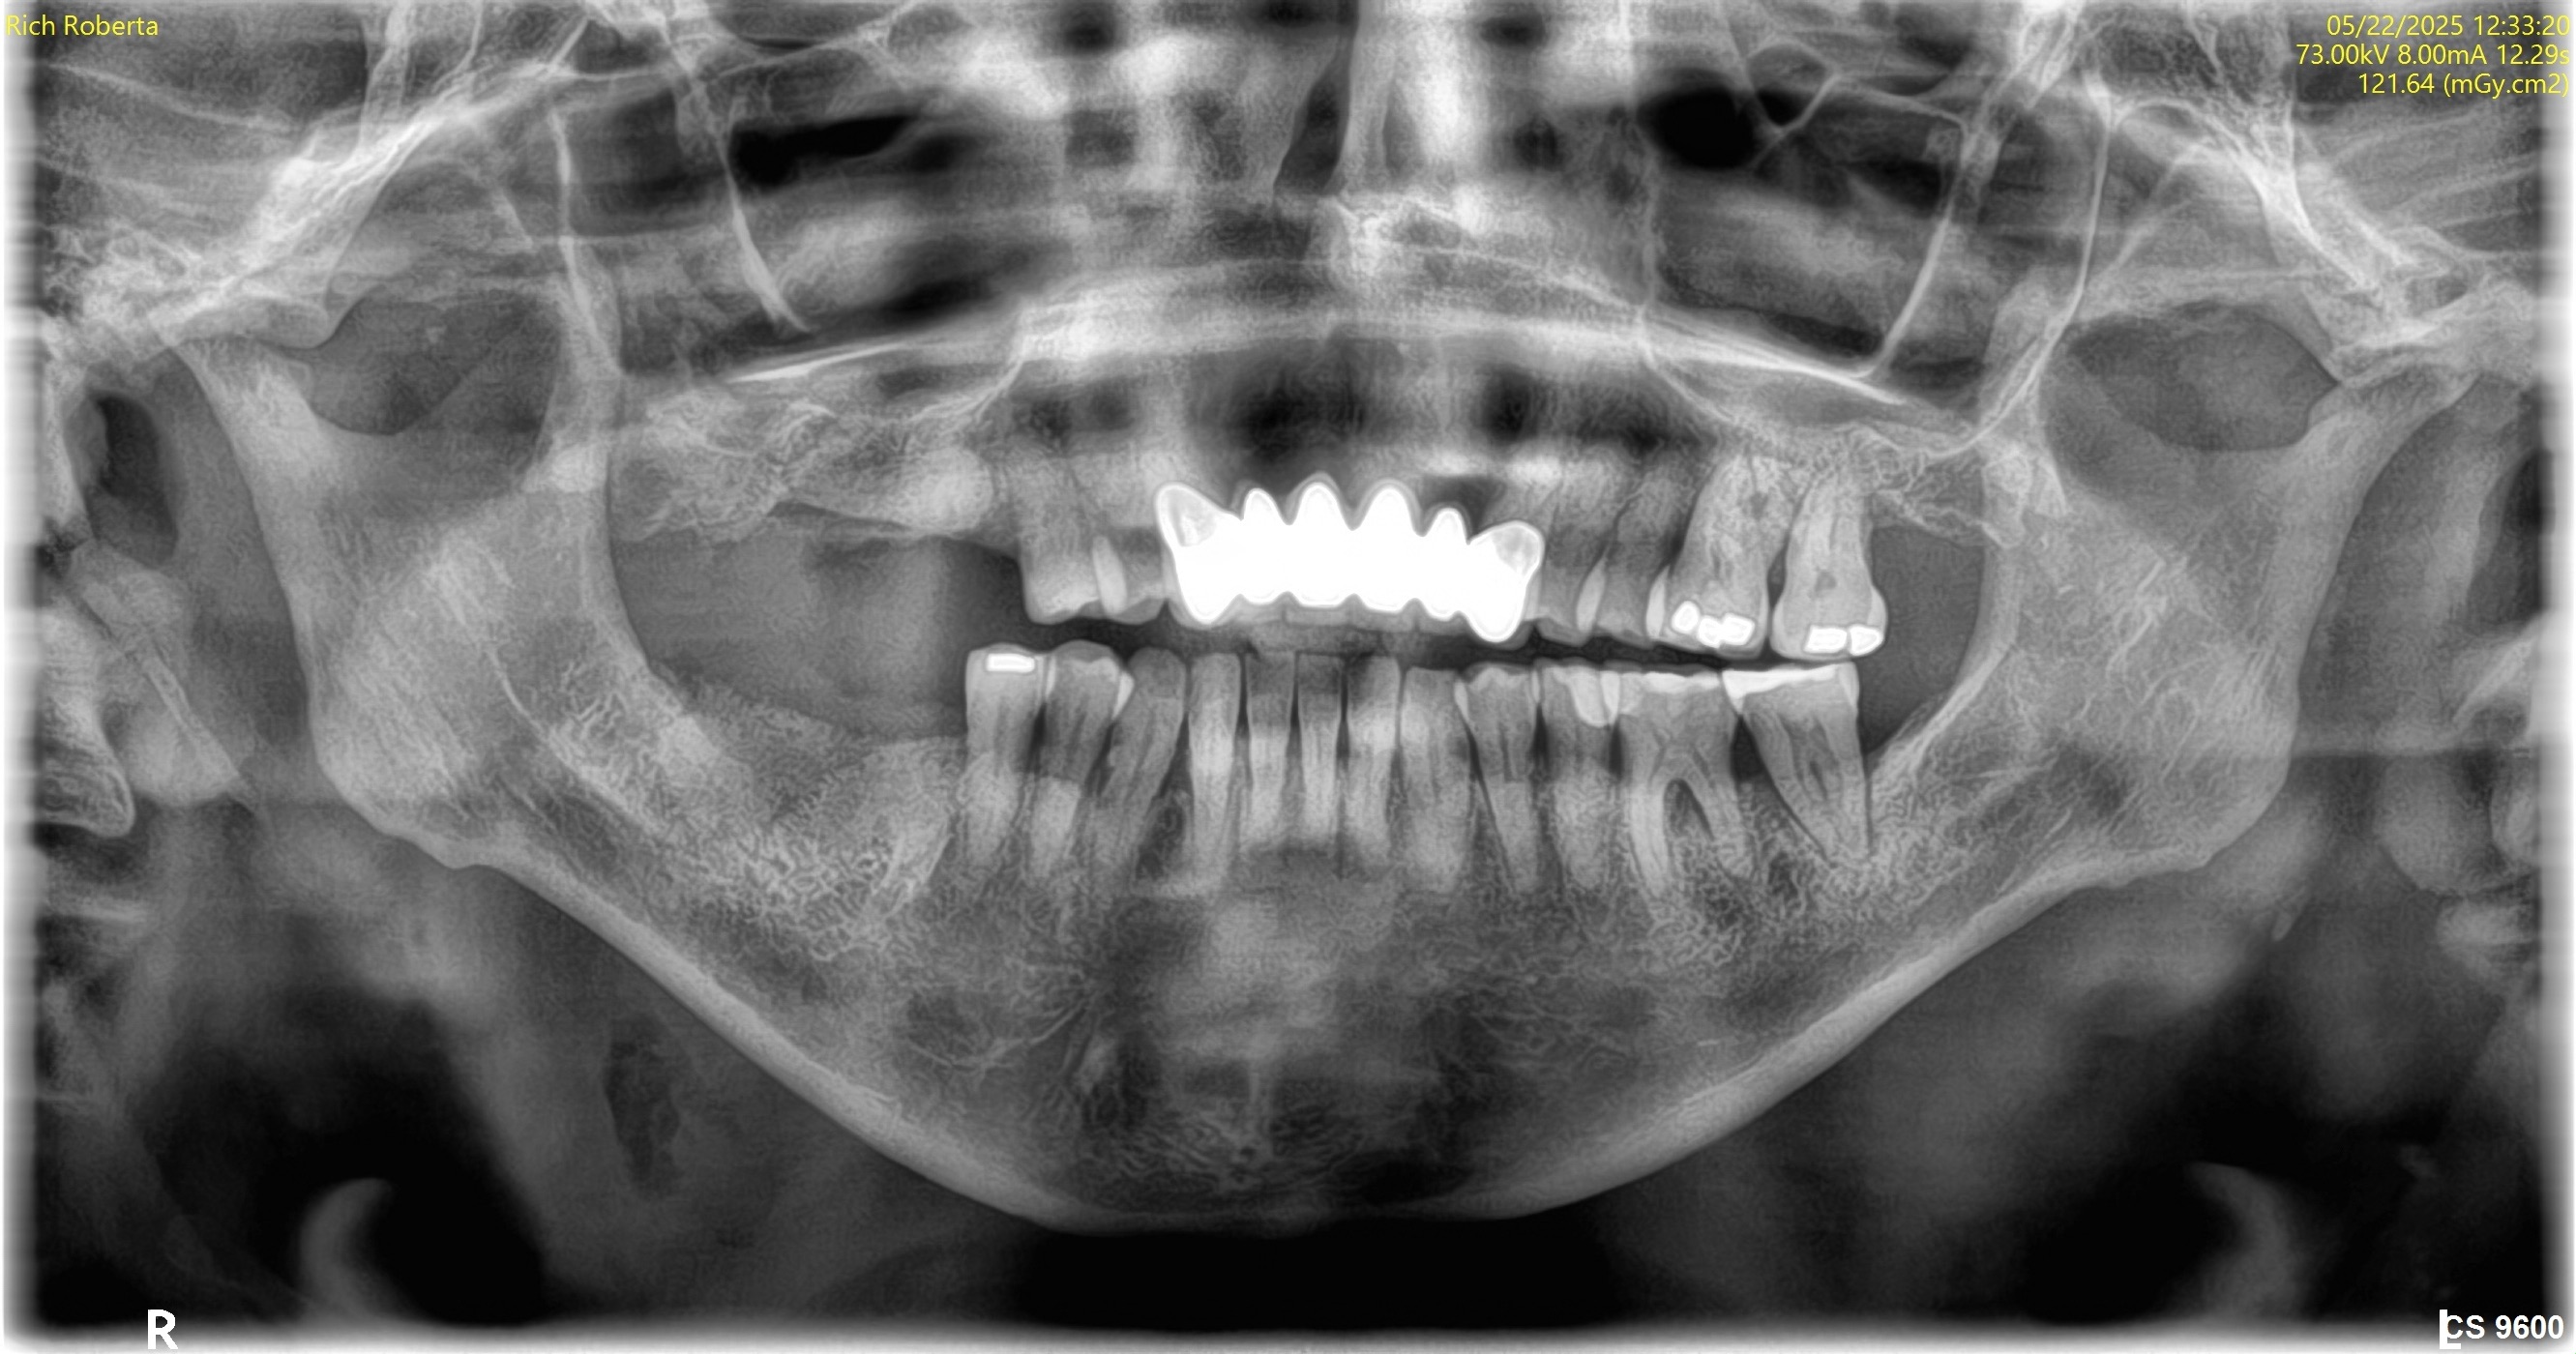

May 22, 2025Extractions with bone grafting (#2, #3, #30, #31) + Covered Socket Residuum (CSR) ~ Previously known as cavitation ~ protocols (#1 and #32) with protection protocol (lower right & upper right).

Visual Case Progression

All clinical images are shown at a consistent size for easy comparison.

Before & After (Pano Images)